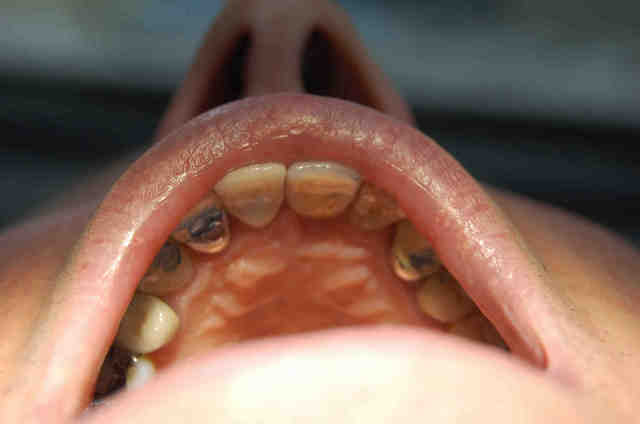

Contact ré-apparu en plein sur le cingulum, et sur la face palatine du bord triturant.

Qui plus est, la couronne parait maintenant près d'1/2 mm plus longue que la voisine.

Ci-joint la photo des contacts photographiés lors de la précédente visite (13/05, après retouches occlusales), et la radio de ce jour.